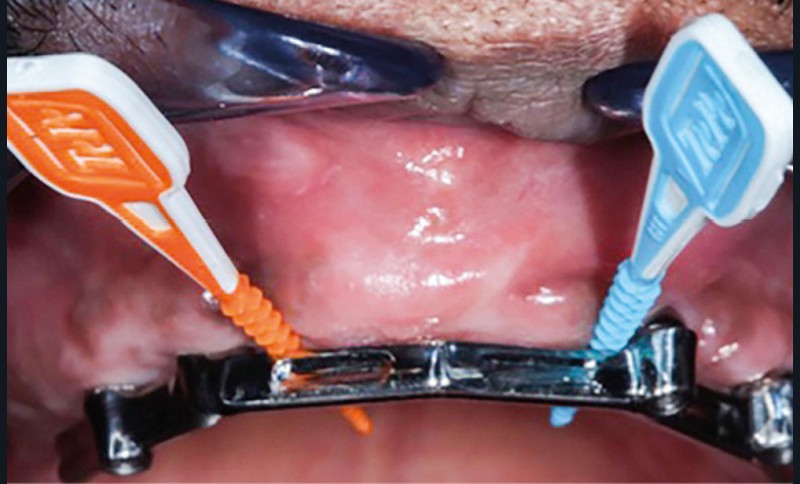

Enfin, la conception prothétique elle-même est à réfléchir, que ce soit en termes de profil d’émergence [18, 19] (pas de surcontour par exemple) (fig. 8) que d’accès à l’hygiène [20, 21] (fig. 9).